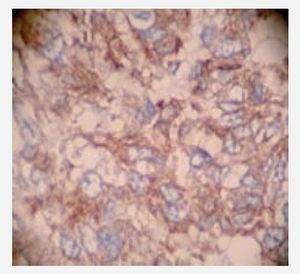

Se trata de paciente del sexo femenino de 47 años de edad, multípara (GVIII, PVIII), sin antecedentes quirúrgicos, ni sintomatología previa a su ingreso. Su cuadro clínico inició cinco días antes de su ingreso, con dolor abdominal en epigastrio e hipocondrio izquierdo, que fue en aumento en los días posteriores, acompañado de vómitos no sanguinolentos. En la exploración del abdomen se encontraron signos de síndrome abdominal agudo, con rebote positivo, hiperestesia e hiperbaralgesia. Los exámenes de laboratorio mostraron hemoglobina de 10.4 g/dL, hematocrito de 30%, leucocitos de 6500/dL, plaquetas de 192,000/dL. La química sanguínea, amilasa, lipasa y tiempos de coagulación fueron normales. El examen general de orina mostró hematuria microscópica y la tele-radiografía de tórax demostró derrame basal izquierdo. La radiografía simple del abdomen evidenció la presencia de asa centinela en intestino delgado. Se decidió realizar laparotomía exploradora en la que se encontró un tumor abscedado de la curvatura mayor del estómago, de 5 cm, de forma ovoide irregular y de consistencia dura. Se realizó gastroyeyuno-anastomosis y esplenectomía (Figura 1). El diagnóstico histopatológico fue de sarcoma gástrico (Figura 2). El estudio de inmunohistoquímica fue positivo para CD 117 y CD 34 (Figuras 3 y 4). El diagnóstico definitivo se definió como sarcoma del estroma gastrointestinal originado de las células de Cajal.

Figura 3. Diagnóstico definitivo: sarcoma del estroma gastrointestinal

Figura 4. Diagnóstico definitivo: sarcoma del estroma gastrointestinal